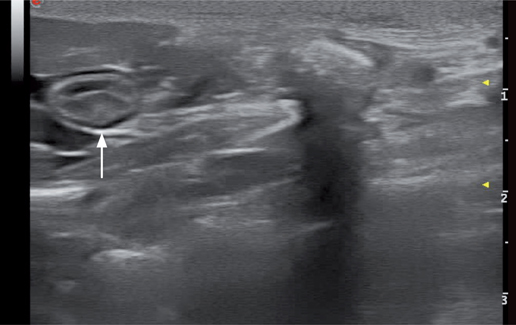

胰管作为胰腺分泌功能的总导管,与总胆管共同汇入十二指肠大乳头。十二指肠大乳头在十二指肠壁上呈一高回声小结节,宽度在2.9-5.5mm(图7)。